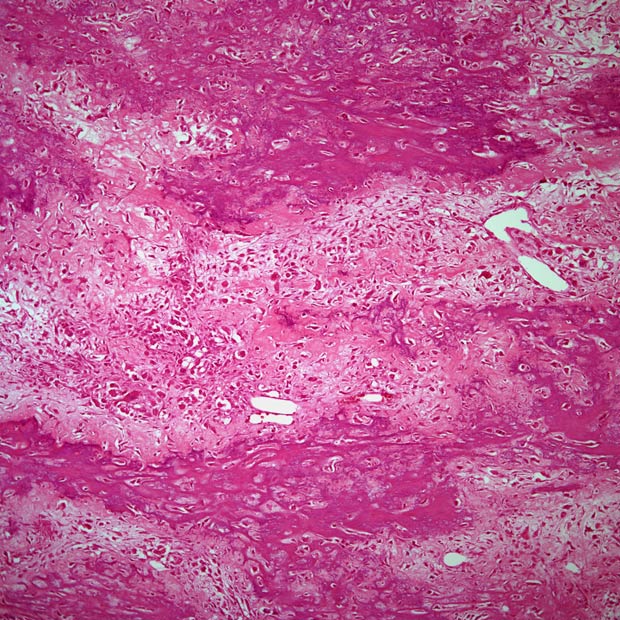

Regarding tumor subtype, 39 and 19 patients in the triplet and single-agent arms, respectively, had a diagnosis of leiomyosarcoma; 2 and 1 patient had dedifferentiated liposarcoma; 2 and 3 patients had undifferentiated pleomorphic sarcoma; and 26 and 13 patients had a disease histology classified as “other.”

Patients who responded to the cabozantinib/nivolumab/ipilimumab regimen had angiosarcoma, epitheliod sarcoma, and myxofibrosarcoma. Both patients who responded to cabozantinib had leiomyosarcoma.